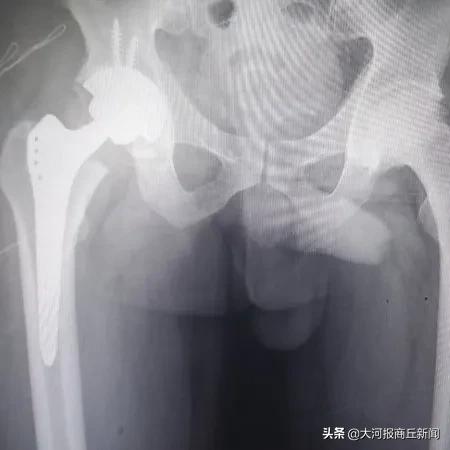

3月2日下午,豫东名医、骨科专家殷晓东院长领衔的柘城县中医院骨科团队在短短三个小时内完成四台人工膝、髋关节置换,其中包含一例高难度高龄患者双髋关节置换,非常时期下骨科团队丰富的经验和精准的操作技术再显不凡身手,较平均用时节约了一半时间,是柘城中医院开展关节置换技术多年来再次跑出的中医院新速度。

▲精技术,强疗效——关节置换重塑健康人生

近年来,柘城中医院骨科一直致力于引进国内外各项先进技术,用于治疗骨关节疾病。在治疗股骨头坏死、膝关节骨性关节炎以及腰间盘突出症等疾病方面形成了独特的三阶梯式治疗方法。术后第二天即可下床走路,快速康复重建关节功能,截止目前,已成功完成了多例多关节同时置换及数十例百岁老人置换病例,受到了患者们的广泛赞誉。